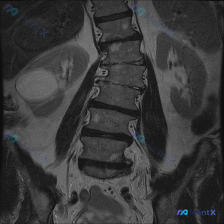

只看这张腰椎MRI冠状位,除了明显的侧弯,还有两个容易漏的关键发现

整理到一张腰椎MRI T2加权序列冠状位的影像资料,先不看后续的其他序列和临床信息,只看这张图的话,有几个点比较值得拿出来讨论: 1. 脊柱力线确实有明显异常,侧弯方向和顶端位置也比较清楚 2. 椎间盘的信号和椎间隙高度有非对称性改变 3. 扫描野里除了腰椎,还能看到双侧肾脏,肾盂肾盏区似乎有信号变...

整理了一张腰椎MRI T2序列冠状位图像的资料,大家可以先看看核心影像表现: - 腰椎整体向右侧凸(凸向右侧,凹向左侧) - 各椎体高度大致正常,边缘可见骨赘形成 - 腰椎下段(L4-L5、L5-S1)椎间隙不对称,凹侧更紧凑 - 冠状位上左侧下方椎间孔区域脂肪信号略显模糊,空间受限 没有提供患者的...

整理到一份腰椎MRI-T2冠状位的影像资料,第一眼就能看到明确的脊柱侧弯——腰椎呈C型向左侧凸。 但仔细看还有几个点: 1. 侧弯凸侧(右侧)椎体边缘有不同程度骨赘形成 2. 双侧小关节增生明显,关节周围有高信号 3. 椎间隙左右不对称,凹侧(左侧)椎间孔空间看起来受压缩 4. 目前层面没看到明确的...

网上看到一份腰椎MRI T2序列冠状位的影像资料,先抛出来和大家讨论一下读片思路。 影像里看到的主要信息整理了一下: - 脊柱序列:腰椎生理曲度轻度侧弯,凸向左侧,各椎体排列基本连续,没看到明显滑脱错位 - 椎体与骨髓:各腰椎椎体形态大致规则,边缘有轻度骨质增生;骨髓T2信号均匀高信号,没看到明显异...

整理到一份腰椎MRI T2冠状位的影像资料,大家先看一眼: 核心影像表现: - 腰椎明显向左侧弯曲,呈“C”型,顶点在腰椎中部 - 椎体形态基本完整,未见明确骨质破坏或压缩 - 椎间盘T2信号普遍减低(偏暗),提示脱水退变 - 侧弯节段椎间隙左右不对称:右侧张开,左侧闭合 - 两侧旁椎肌肉(腰大肌、...

整理到一份腰椎MRI T2序列冠状位的影像分析,第一眼确实很容易被「脊柱侧弯」抓住注意力——影像上腰椎序列明显向左侧弯,多节段椎间盘T2信号减低,椎间隙左右不对称,典型的退行性改变表现。 但再看下去,右肾区有一个圆形的T2高信号灶,报告里单独提了这个「除脊柱以外最显著的异常发现」。 如果只看到前期的...

整理到一份影像读片资料,有点意思,放出来讨论下。 先看核心发现: - 腰椎MRI T2冠状位:明显向左侧凸畸形;椎体边缘骨赘形成,部分椎间隙非对称性变窄;凹侧椎间孔区域相对狭窄。 - 额外发现:右侧(图像左侧)肾脏内见边界尚清的明显高信号影。 影像科初步分析里提了“退行性脊柱侧弯”的依据很足,但同时...